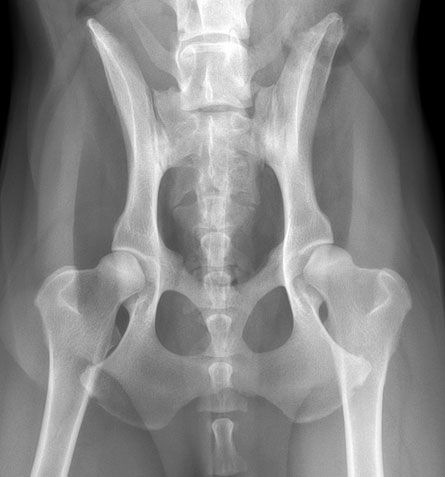

Hüfte mit Arthrose

Dieser 7 jährige, etwa gleichgrosse Rüde hat eine deutliche HD, rechts mit stärkerer Arthrose als links. Der Hüftkopf verliert seine runde glatte Form. Deutliche Arthrose schmerzen sind die Folge.